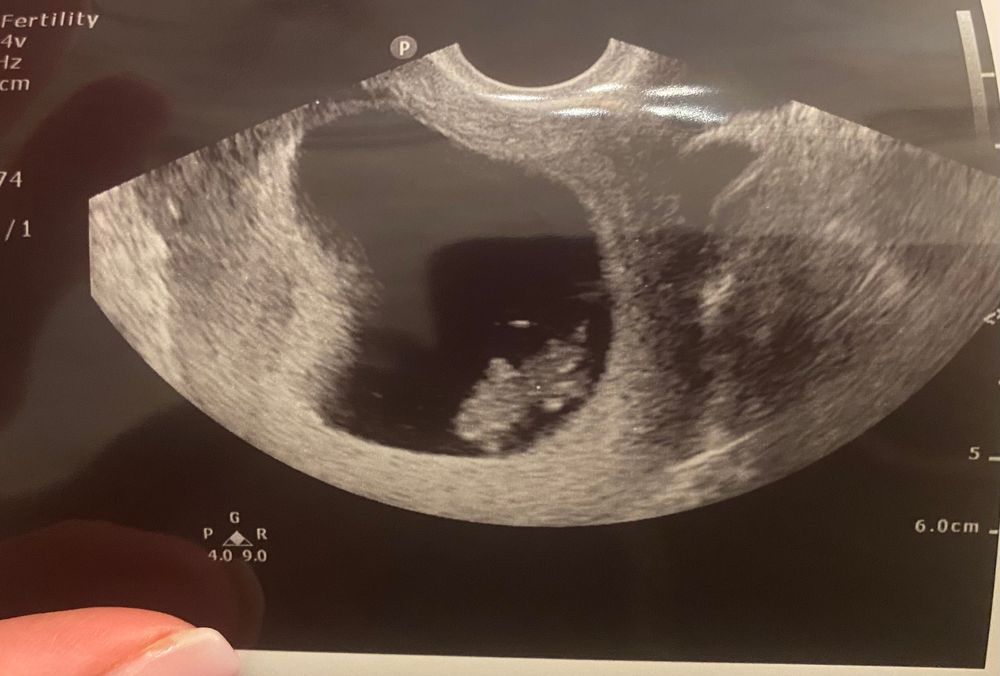

Привет, малыш ❤️